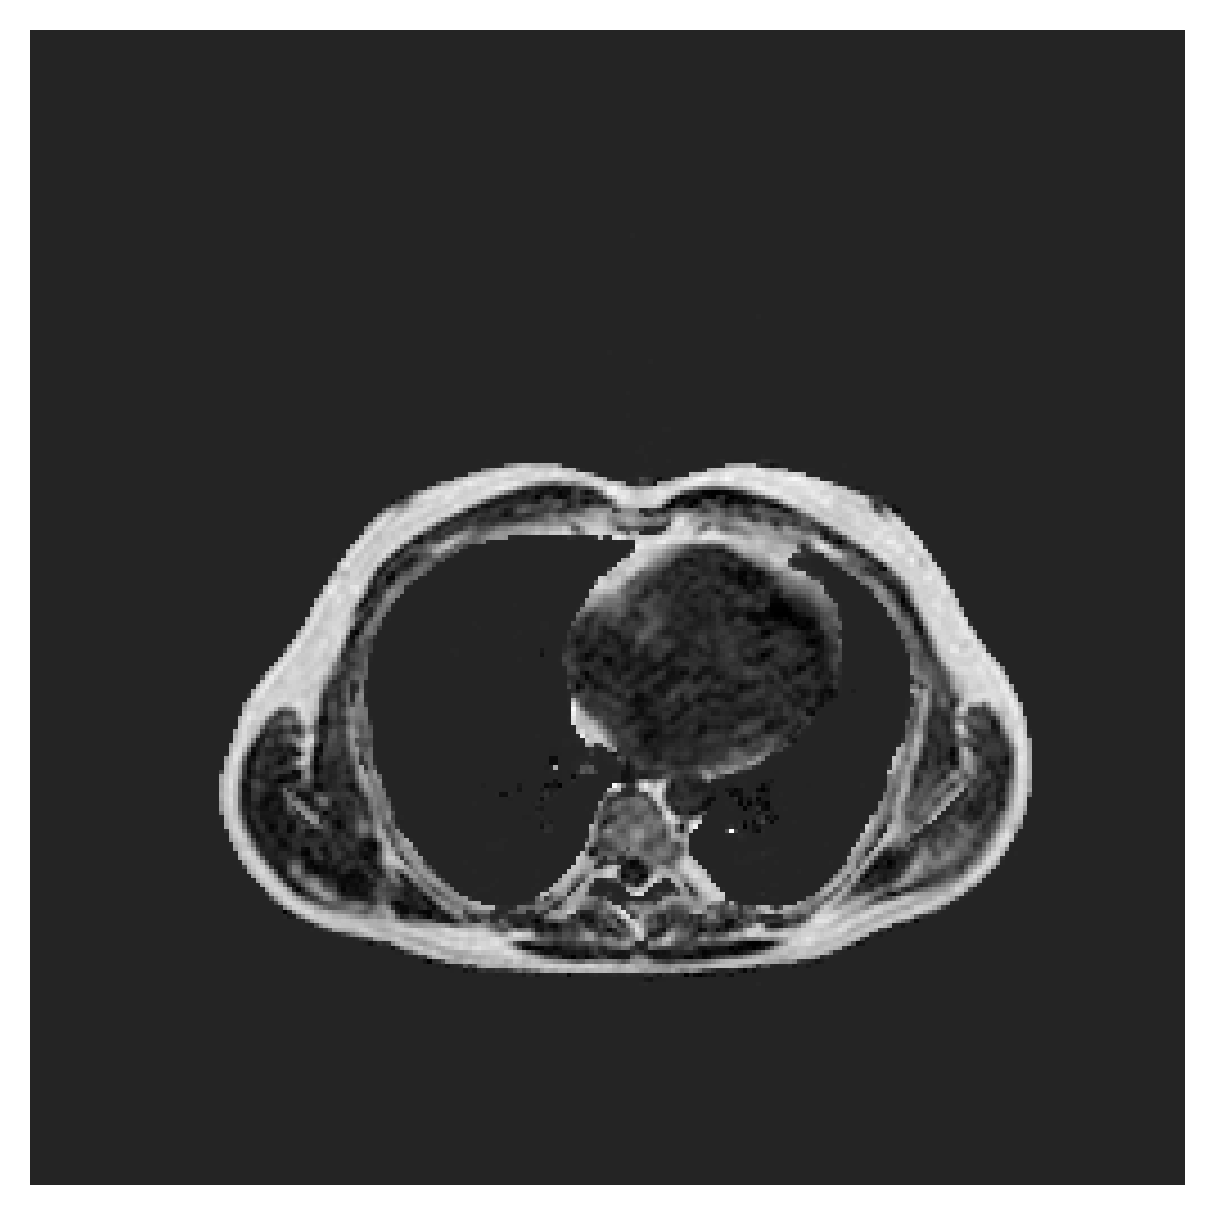

ACDC

([5]) The Automated Cardiac Diagnosis Challenge (ACDC) is a public benchmark multi-class heart segmentation dataset. It contains cine-MR images of 150 patients (of which 100 are available for training and the rest 50 comprise a test set), covering healthy scans and four types of pathologies in equal amounts, with annotations for the right ventricle (RV), myocardium (Myo) and left ventricle (LV) heart structures. We split the training set randomly, using 65 subjects for training, 10 for validation and 25 as a hold-out test set. Due to the large and varying interslice gap, we work with 2D slices instead of 3D volumes directly. This includes distance map computation.

We normalize the volumes and resize the slices to pixels. As the official dataset comes with full annotations, we create a synthetic point ground truth. This is done by first randomly choosing the centers of the point annotations within the class masks, followed by filling an ellipse with axes lengths of and (in pixels) around each center. The intersections of these elliptic discs with the underlying full annotations are then used as our point ground truth. See Figure 2 for an example of the created weak annotation mask. The point annotations are created for every slice, one for each foreground object present in the slice.

5.1 Segmentation of cardiac structures

The average 3D Dice scores and HD95 values on the ACDC test set are given in Table 2, and boxplots in figures 4 and 5 show the distributions. We see that, in terms of DSC, the proposed strategy of using intensity-aware distances withing boundary loss performs better than simply using the Euclidean distance, with the best results achieved by using the strictly intensity based MBD. The HD95 however favors the original version of , which may be do to its smoother predictions and less fragmentation and oversegmentation. The CRF-loss results are significantly worse in both metrics.

In Figure 3 we show the 3D DSC validation curve evolution for a single run. The CRF-loss seems to have converged to a low DSC value, while all settings combining CE and boundary loss reach values close to the full supervision in the beginning of the training and then slowly collapse towards to the point annotations. The MBD version stands out, degrading slower, thus providing a wider range of potentially good models for evaluation.

Qualitative comparison

In Figure 6 we provide qualitative results on a number of randomly chosen test set slices. Upon visual inspection, we can observe that training with the intensity-aware distances (particularly with and ) follows the image gradients better and is better at recovering the underlying shape than the Euclidean version. The CRF-loss seems to recover the shape of the myocardium and left ventricle to some extent, but fails entirely on the right ventricle.